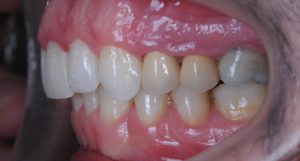

Maloclusión clase II

Se caracteriza por una relación anormal entre los dientes superiores e inferiores, donde los dientes superiores están demasiado adelantados en comparación con los inferiores.

Esto puede generar problemas funcionales, como dificultad para masticar, y también afectar la estética facial.